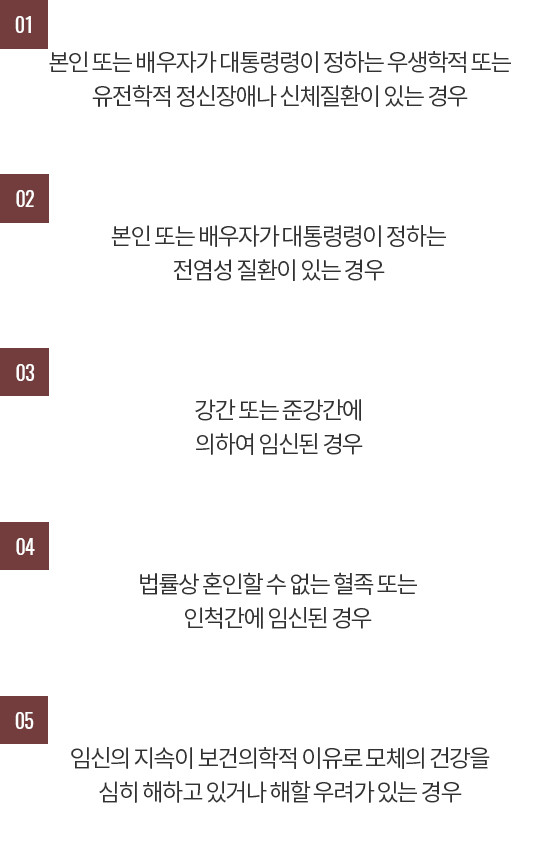

중절수술 후 회복과정에서 나타나는 증상

중절수술을 하게 되면 유산 당일 수술 직후부터 생리통과 같은 아랫배 통증이 있을 수 있습니다.

진통제를 사용하게 되면 도움이 되지만 수술 직후에는 과다 자궁출혈을 예방하기 위해 자궁수축제를 사용함으로써

통증이 심한 경우도 있으므로 하복부의 통증이 오히려 자궁수축에 도움이 되기도 합니다.

자궁수축과 관련되어 아랫배의 통증이 너무 심할 경우에는 자궁의 근육이 과도하게 수축되는 것을 풀어주고

적절한 자궁근육 이완을 도와주는 보조적인 치료가 필요하기도 합니다.

어지러움과 빈혈 증세를 느끼고 식은땀이나 현기증을 느끼기도 합니다.

심한 경우 구토나 위장장애가 동반되기도 합니다.

중절수술 이후 일정기간은 출혈이 보이는데요.

출혈은 수술을 받을 당시의 임신 주수에 따라 1주~ 3주 가까이 자궁 출혈이 지속되기도 합니다.